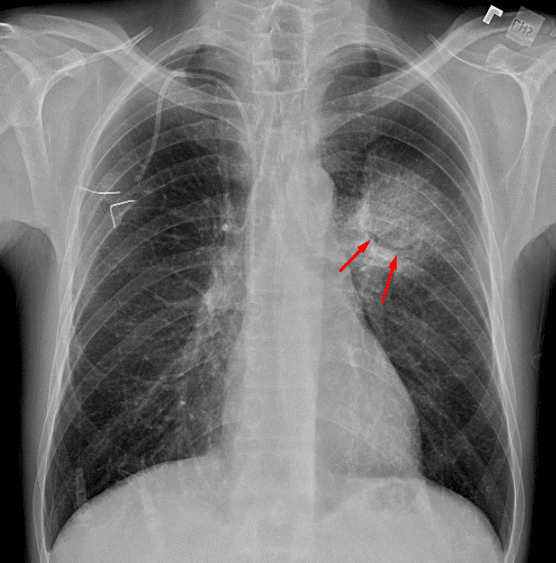

- Rounded opacity centered in the superior segment of the left lower lobe with a crescent of air noted. The opacity does not appear to displace or cross the major fissure

Rounded opacity centered in the superior segment of the left lower lobe with a crescent of air noted along its inferior aspect. This appearance is concerning for atypical pneumonia, in particular invasive aspergillosis. Consider chest CT for further evaluation.

- Angioinvasive subtype: nodular opacities with groundglass halos or peripheral wedge shaped areas of consolidation. Air crescent sign can be seen during the healing phase as tissue necroses and retracts

Rounded opacity centered in the superior aspect of the left lower lobe with an air crescent (red arrows).